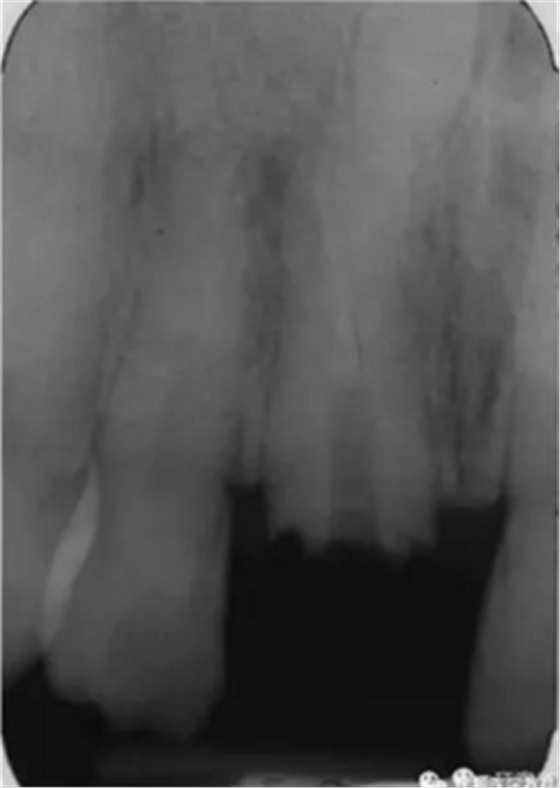

本例患者為男性,53歲,由于右上頜中切牙疼痛,在蘇格蘭的格拉斯哥口腔醫(yī)院就診。根管治療后1年來牙齒出現(xiàn)自發(fā)性疼痛。檢查發(fā)現(xiàn)患者冠部修復(fù)體3周前丟失,未發(fā)現(xiàn)竇道,牙面較多部位探診時患者較敏感,說明牙齒仍為活髓,可以修復(fù)?;颊呱眢w狀況良好。影像學(xué)顯示,患牙根尖彎曲處充填不充分,根尖周有陰影,還發(fā)現(xiàn)在右上頜中切牙的根尖部有一倒置的額外牙顯影,周圍牙周膜寬度正常。

圖1. 治療前患牙根尖周顯影